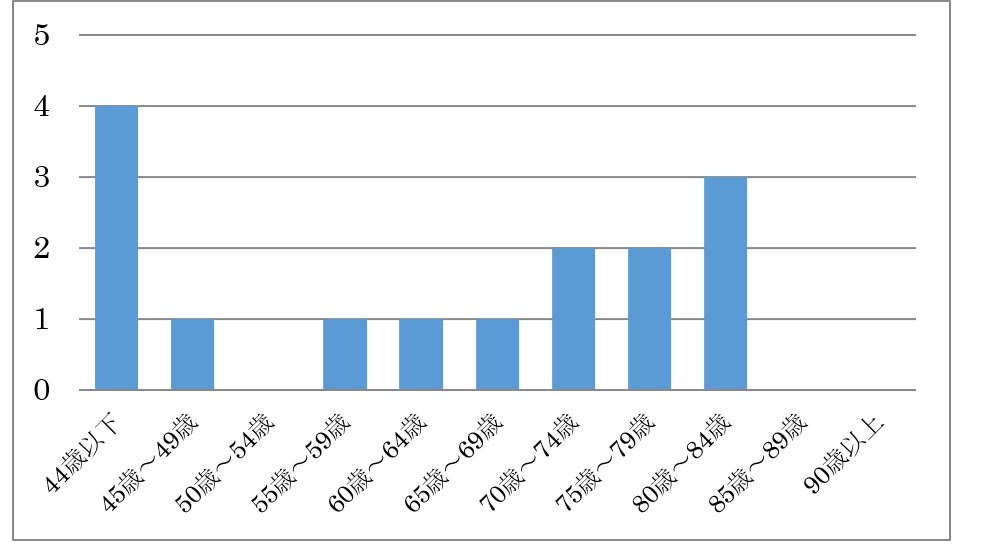

Q. 橈骨神経麻痺の発症年齢は何歳ぐらいですか?

A. 2016年1月~2018年6月30日まで通院された新規の患者さんは2年6か月で15名の年齢分布です。1年間で6名程度の新規発生です。40代以下と70歳以降に増加傾向があります。